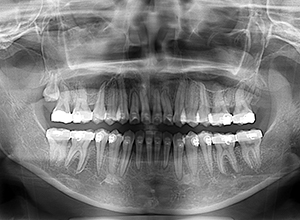

初診時

X-Ray

X-Ray所見

パノラマ所見 右上8は埋伏していた。右下4根尖部付近にセメント質腫様所見が認められた。